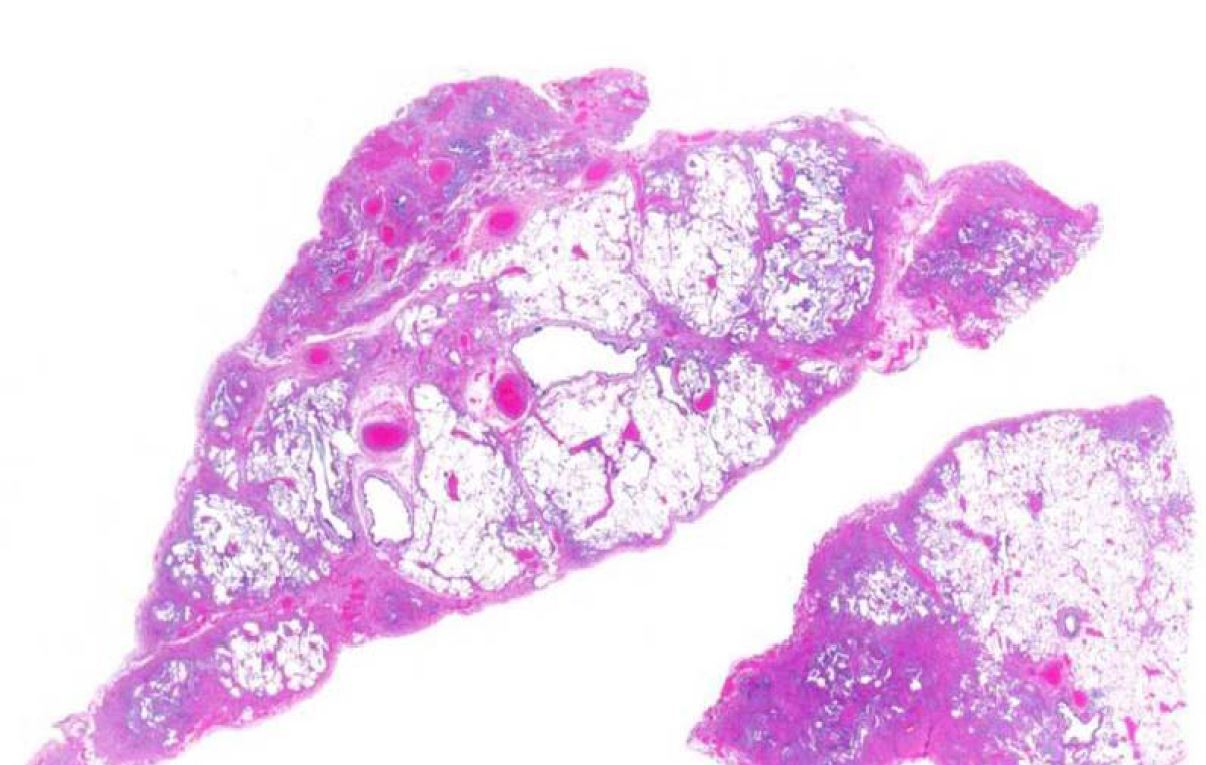

This lesion in the lung is seen more commonly in women with an average age in the 40s and shows papillary like projections lined by epithelioid cells with a central proliferation of polygonal mesenchymal appearing cells. Both populations are TTF1 positive indicating type II pneumocyte origin for this tumor.

Sclerosing hemangioma of the lung